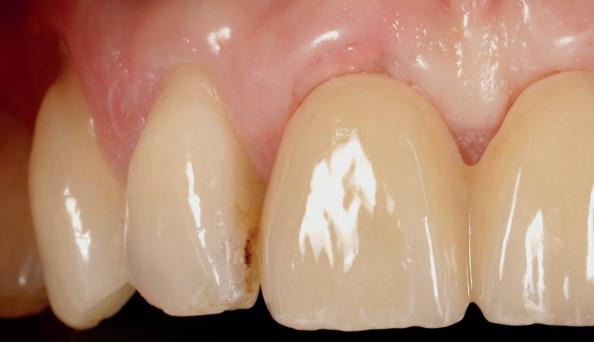

Adults could one day grow their own replacement teeth instead of having fillings – as scientists make a key discovery. This research offers a potential way to repair teeth and a natural dental treatment alternative.

While some animals like sharks and elephants can continuously grow new teeth, humans only have one set from adulthood. The ability to regenerate teeth would be a major leap forward for dentistry.

Unlike implants and fillings, which are fixed and cannot adapt over time, a labgrown tooth made from a patient’s own cells could integrate seamlessly into the jaw and repair itself like a natural tooth.

Xuechen Zhang, from the Faculty of Dentistry, Oral & Craniofacial Sciences, King’s College London, said: “Fillings aren’t the best solution for repairing teeth. Over time, they will weaken tooth structure, have a limited lifespan, and can lead to further decay or sensitivity. Implants require invasive surgery and good combination of implants and alveolar bone. Both solutions are artificial and don’t fully restore natural tooth function, potentially leading to long-term complications.”

“Lab-grown teeth would naturally regenerate, integrating into the jaw as

real teeth. They would be stronger, longer lasting, and free from rejection risks, offering a more durable and biologically compatible solution than fillings or implants.”